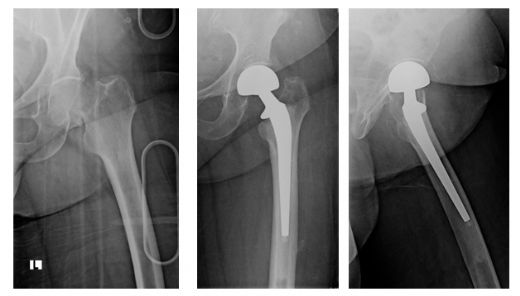

Kalça Kemiği Kırığı Ameliyatı Riskleri ve SonrasıKalça kemiği kırığı, genellikle yaşlı bireylerde görülen ciddi bir yaralanmadır. Bu tür kırıklar, düşme gibi travmatik olaylar sonucunda meydana gelir ve tedavi edilmediği takdirde, hastaların yaşam kalitesini ciddi şekilde etkileyebilir. Ameliyat, kalça kemiği kırığının tedavisinde yaygın bir yaklaşımdır ve bu yazıda, kalça kemiği kırığı ameliyatının riskleri ve sonrasındaki süreç ele alınacaktır. Kalça Kemiği Kırığı Nedir? Kalça kemiği kırığı, femur (uyluk kemiği) başı veya boyu bölgesinde meydana gelen bir kırılmadır. Bu kırıklar, yaşlılık, osteoporoz gibi kemik hastalıkları veya travmatik yaralanmalar sonucu ortaya çıkabilir. Kalça kırıkları, genellikle şiddetli ağrı, hareket kısıtlılığı ve şişlik gibi belirtilerle kendini gösterir. Ameliyatın Gerekçesi Kalça kemiği kırığının cerrahi müdahale ile tedavi edilmesinin başlıca nedenleri şunlardır:

Ameliyat Riskleri Kalça kemiği kırığı ameliyatı, diğer cerrahi işlemler gibi bazı riskleri barındırır. Bu riskler arasında:

Bu riskler, hastanın genel sağlık durumu, yaş ve mevcut diğer sağlık sorunları gibi faktörlere bağlı olarak değişebilir. Ameliyat Sonrası Süreç Ameliyat sonrasında hastaların dikkat etmeleri gereken birkaç önemli husus vardır:

Sonuç Kalça kemiği kırığı ameliyatı, yaşlı bireylerde sıklıkla karşılaşılan bir durumdur ve dikkate alınması gereken önemli riskler içermektedir. Bununla birlikte, doğru bir şekilde uygulanan cerrahi müdahale ve takip eden rehabilitasyon süreci, hastaların yaşam kalitesini artırabilir ve günlük aktivitelerine dönmelerini sağlayabilir. Dolayısıyla, bu tür bir ameliyatın gerekliliği ve riskleri hakkında hastaların ve yakınlarının bilinçli olmaları büyük önem taşımaktadır. Ekstra Bilgiler: Kalça kırığı sonrası komplikasyonlar arasında, hastanın yatakta uzun süre kalması sonucunda ortaya çıkabilecek bası yaraları, kas zayıflığı ve fiziksel yetenek kaybı gibi durumlar da bulunmaktadır. Bu nedenle, ameliyat sonrası dönemde hastaların mümkün olan en kısa sürede hareket etmeleri sağlanmalı ve destekleyici tedavi yöntemleri uygulanmalıdır. |